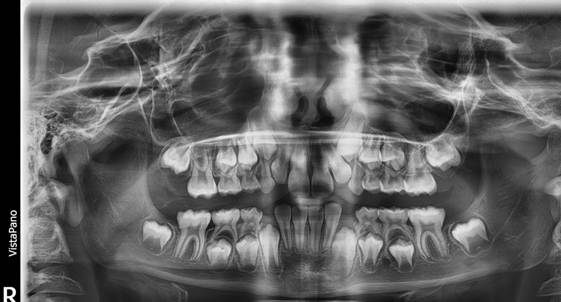

Figura 9. Análisis radiográfico

Al examen radiográfico se observa una dentición mixta.